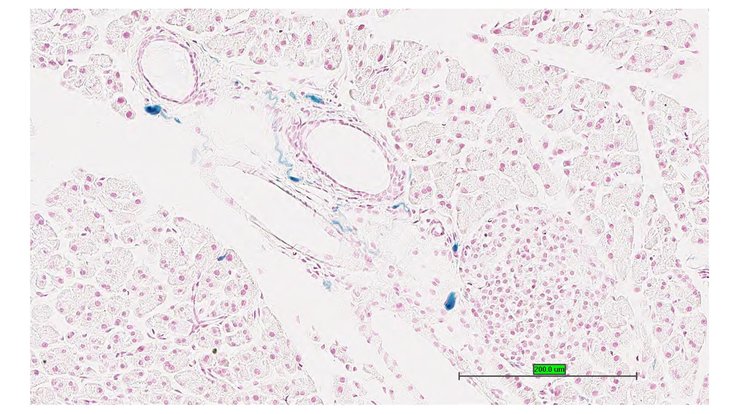

TS28: pancreas Present UC Davis_1876100

Specimen UC Davis_1876101: postnatal adult; Kcna1tm1.1(KOMP)Vlcg/Kcna1+ (more )

TS28: pancreas Present UC Davis_1876031

Specimen UC Davis_1876032: postnatal adult; Kcna1tm1.1(KOMP)Vlcg/Kcna1+ (more )

Structure Level Pattern Image Note

TS28: pancreas Present UC Davis_1876032

Specimen UC Davis_1876033: postnatal adult; Kcna1tm1.1(KOMP)Vlcg/Kcna1+ (more )

TS28: pancreas Present UC Davis_1876033

Specimen UC Davis_1876034: postnatal adult; Kcna1tm1.1(KOMP)Vlcg/Kcna1+ (more )

TS28: pancreas Present UC Davis_1876034